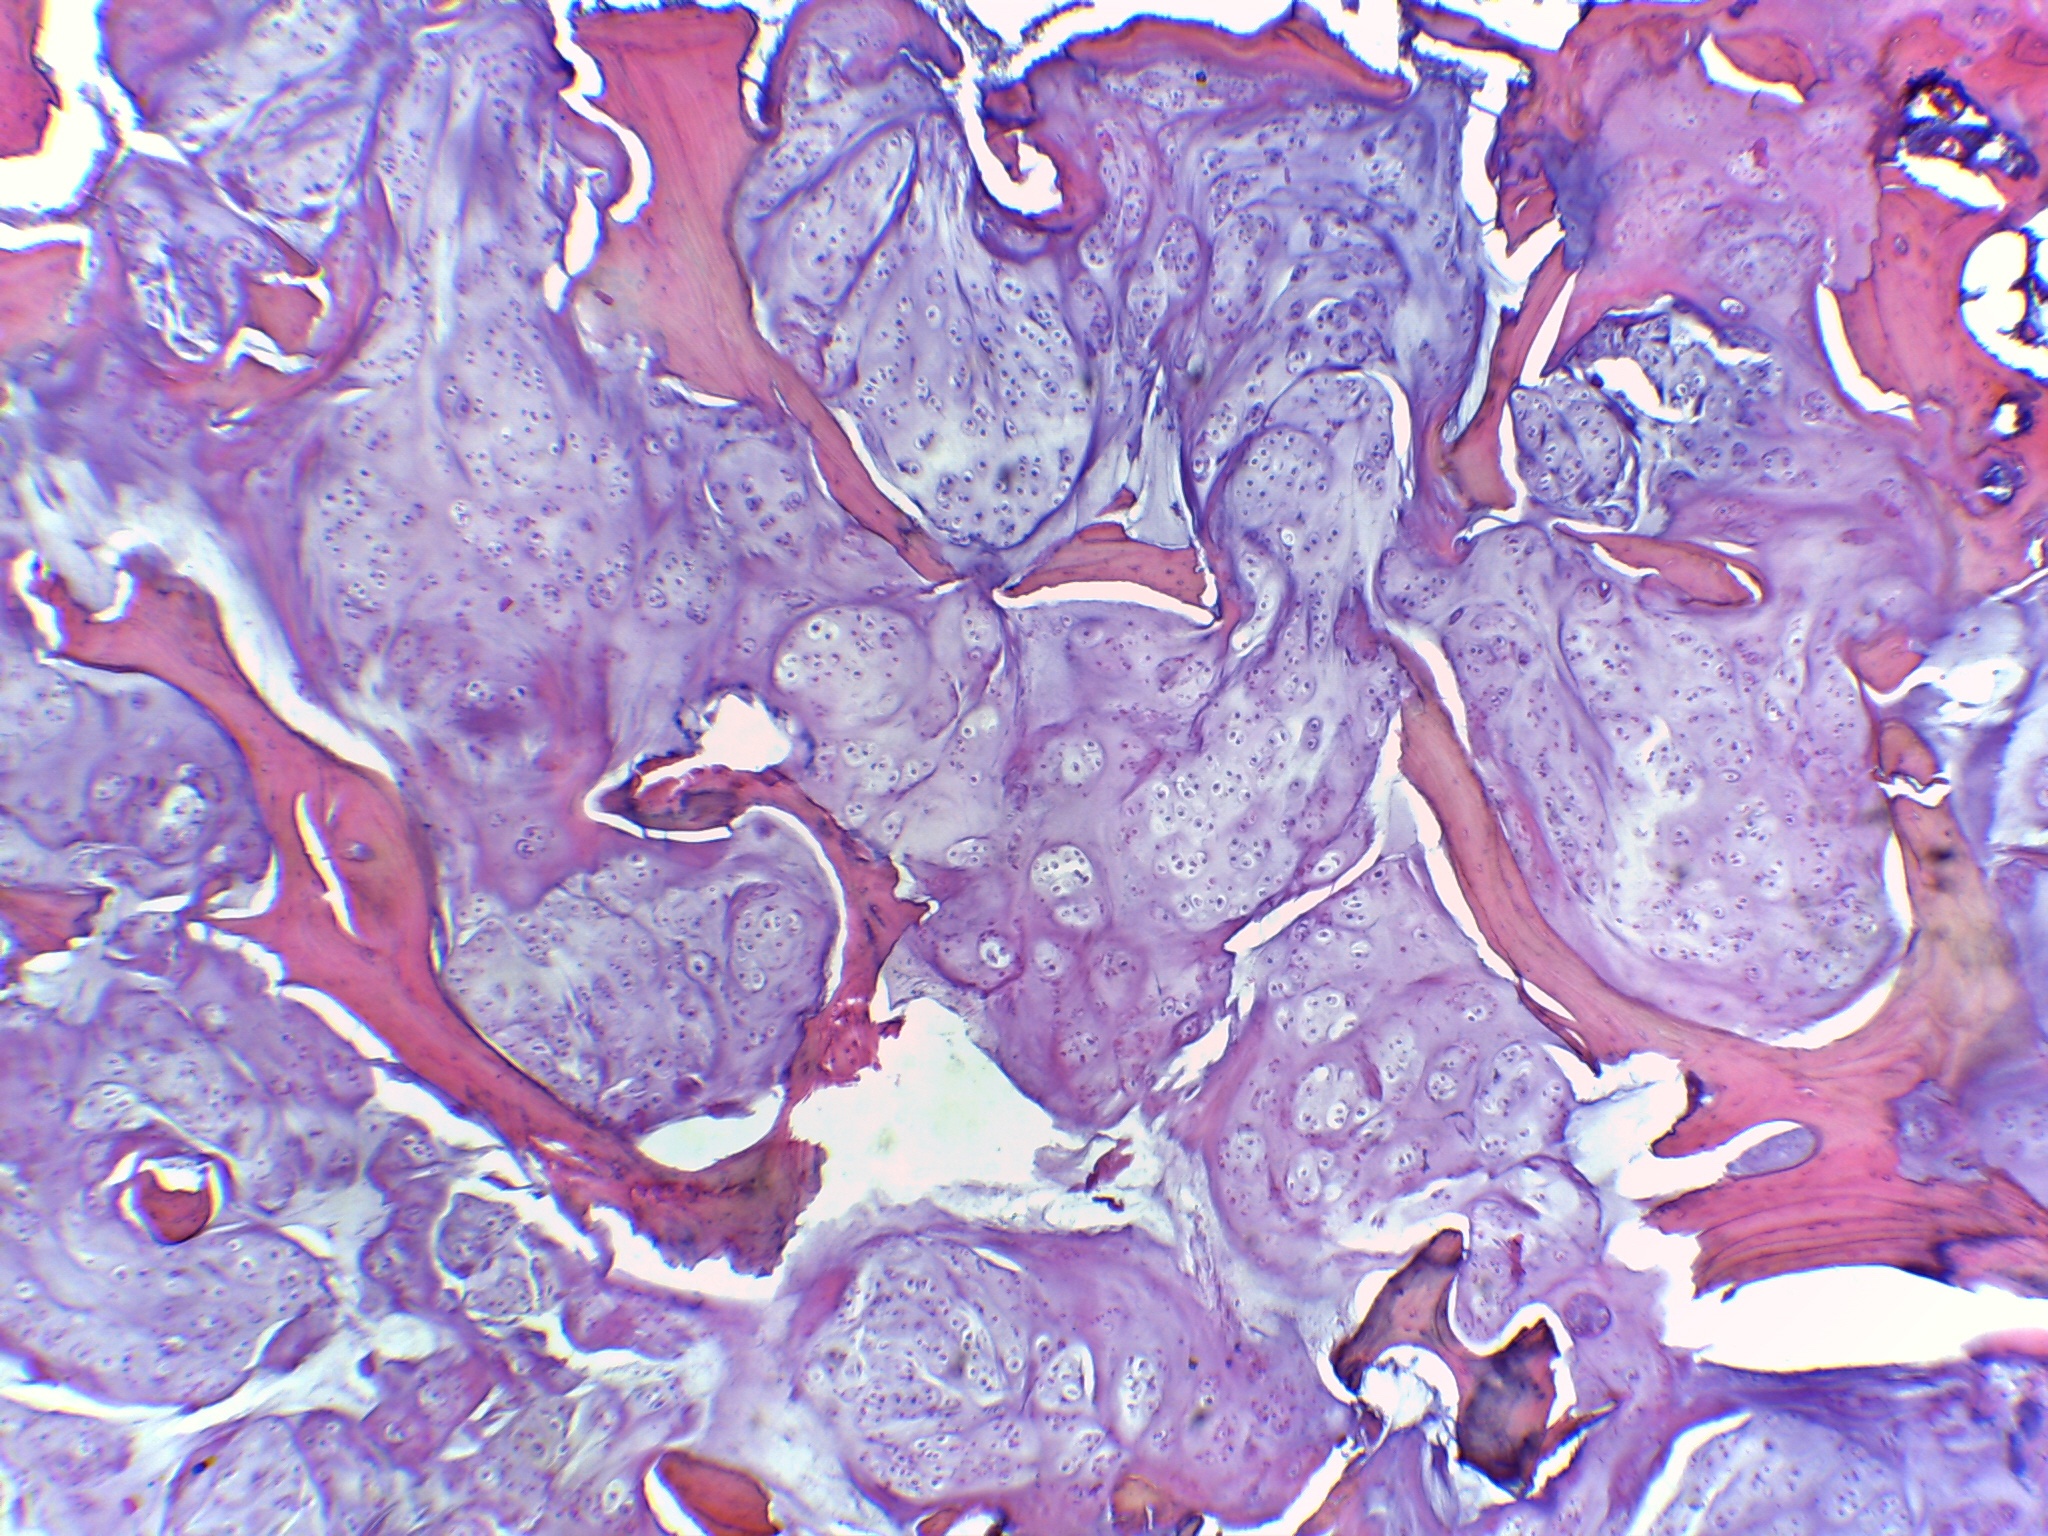

Mujer de 49 años. Dolor en pierna  de 2 años de evolución.

Dolor en pierna  de 2 años de evolución

Incremento de dolor

Fractura de fémur

Condrosarcoma desdiferenciado